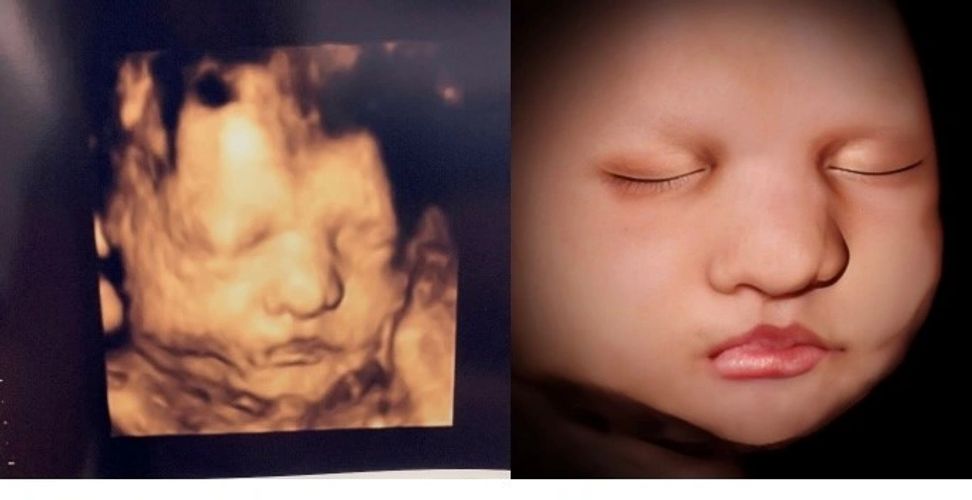

Before After Photo Gallery 3d And 4d Ultrasound Virginia Baby Pictures 3d Ultrasound Baby Ultrasound

What Does A 4d Ultrasound Look Like Quora